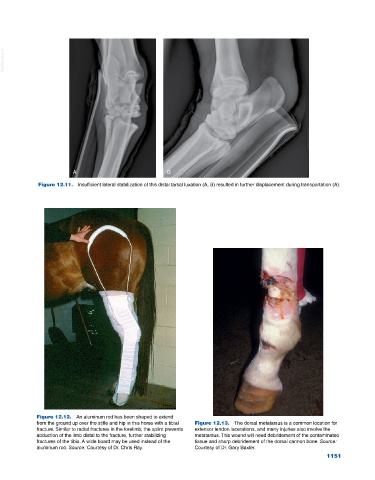

Figure 12.11. Insufficient lateral stabilization of this distal tarsal luxation (A, B) resulted in further displacement during transportation (A).

Figure 12.12. An aluminum rod has been shaped to extend

from the ground up over the stifle and hip in this horse with a tibial Figure 12.13. The dorsal metatarsus is a common location for

fracture. Similar to radial fractures in the forelimb, the splint prevents extensor tendon lacerations, and many injuries also involve the

abduction of the limb distal to the fracture, further stabilizing metatarsus. This wound will need debridement of the contaminated

fractures of the tibia. A wide board may be used instead of the tissue and sharp debridement of the dorsal cannon bone. Source:

aluminum rod. Source: Courtesy of Dr. Chris Ray. Courtesy of Dr. Gary Baxter.